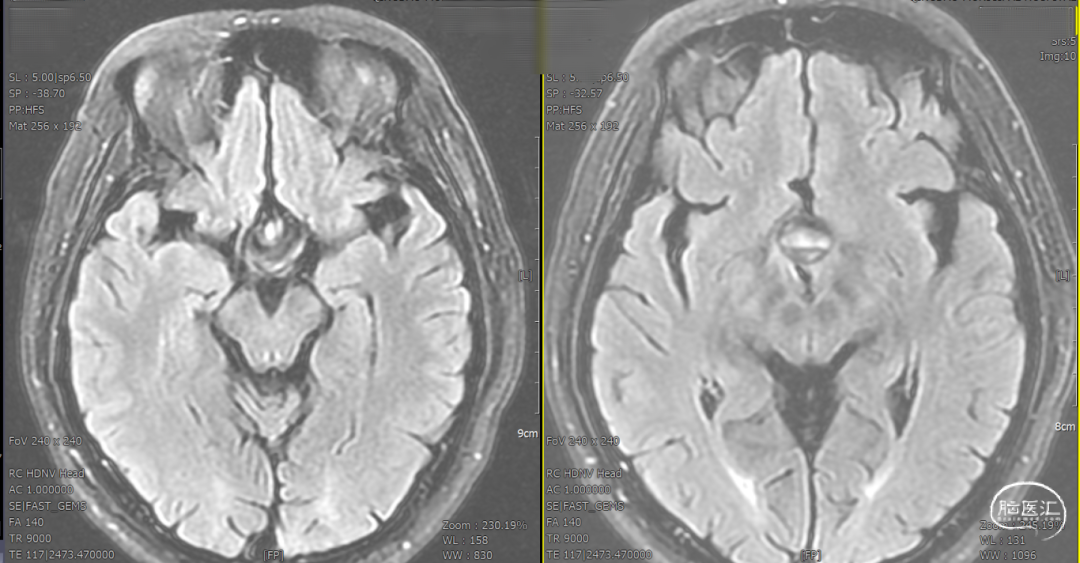

辅助检查示:2025-01-08 鞍区及垂体MR平扫:鞍内及鞍上肿瘤,垂体瘤并卒中?建议鞍区及垂体MR增强扫描。

DSA造影3D重建测量

支架置入后造影显示,瘤内滞留明显,对侧造影几乎未见瘤内造影剂显影,手术结果满意。